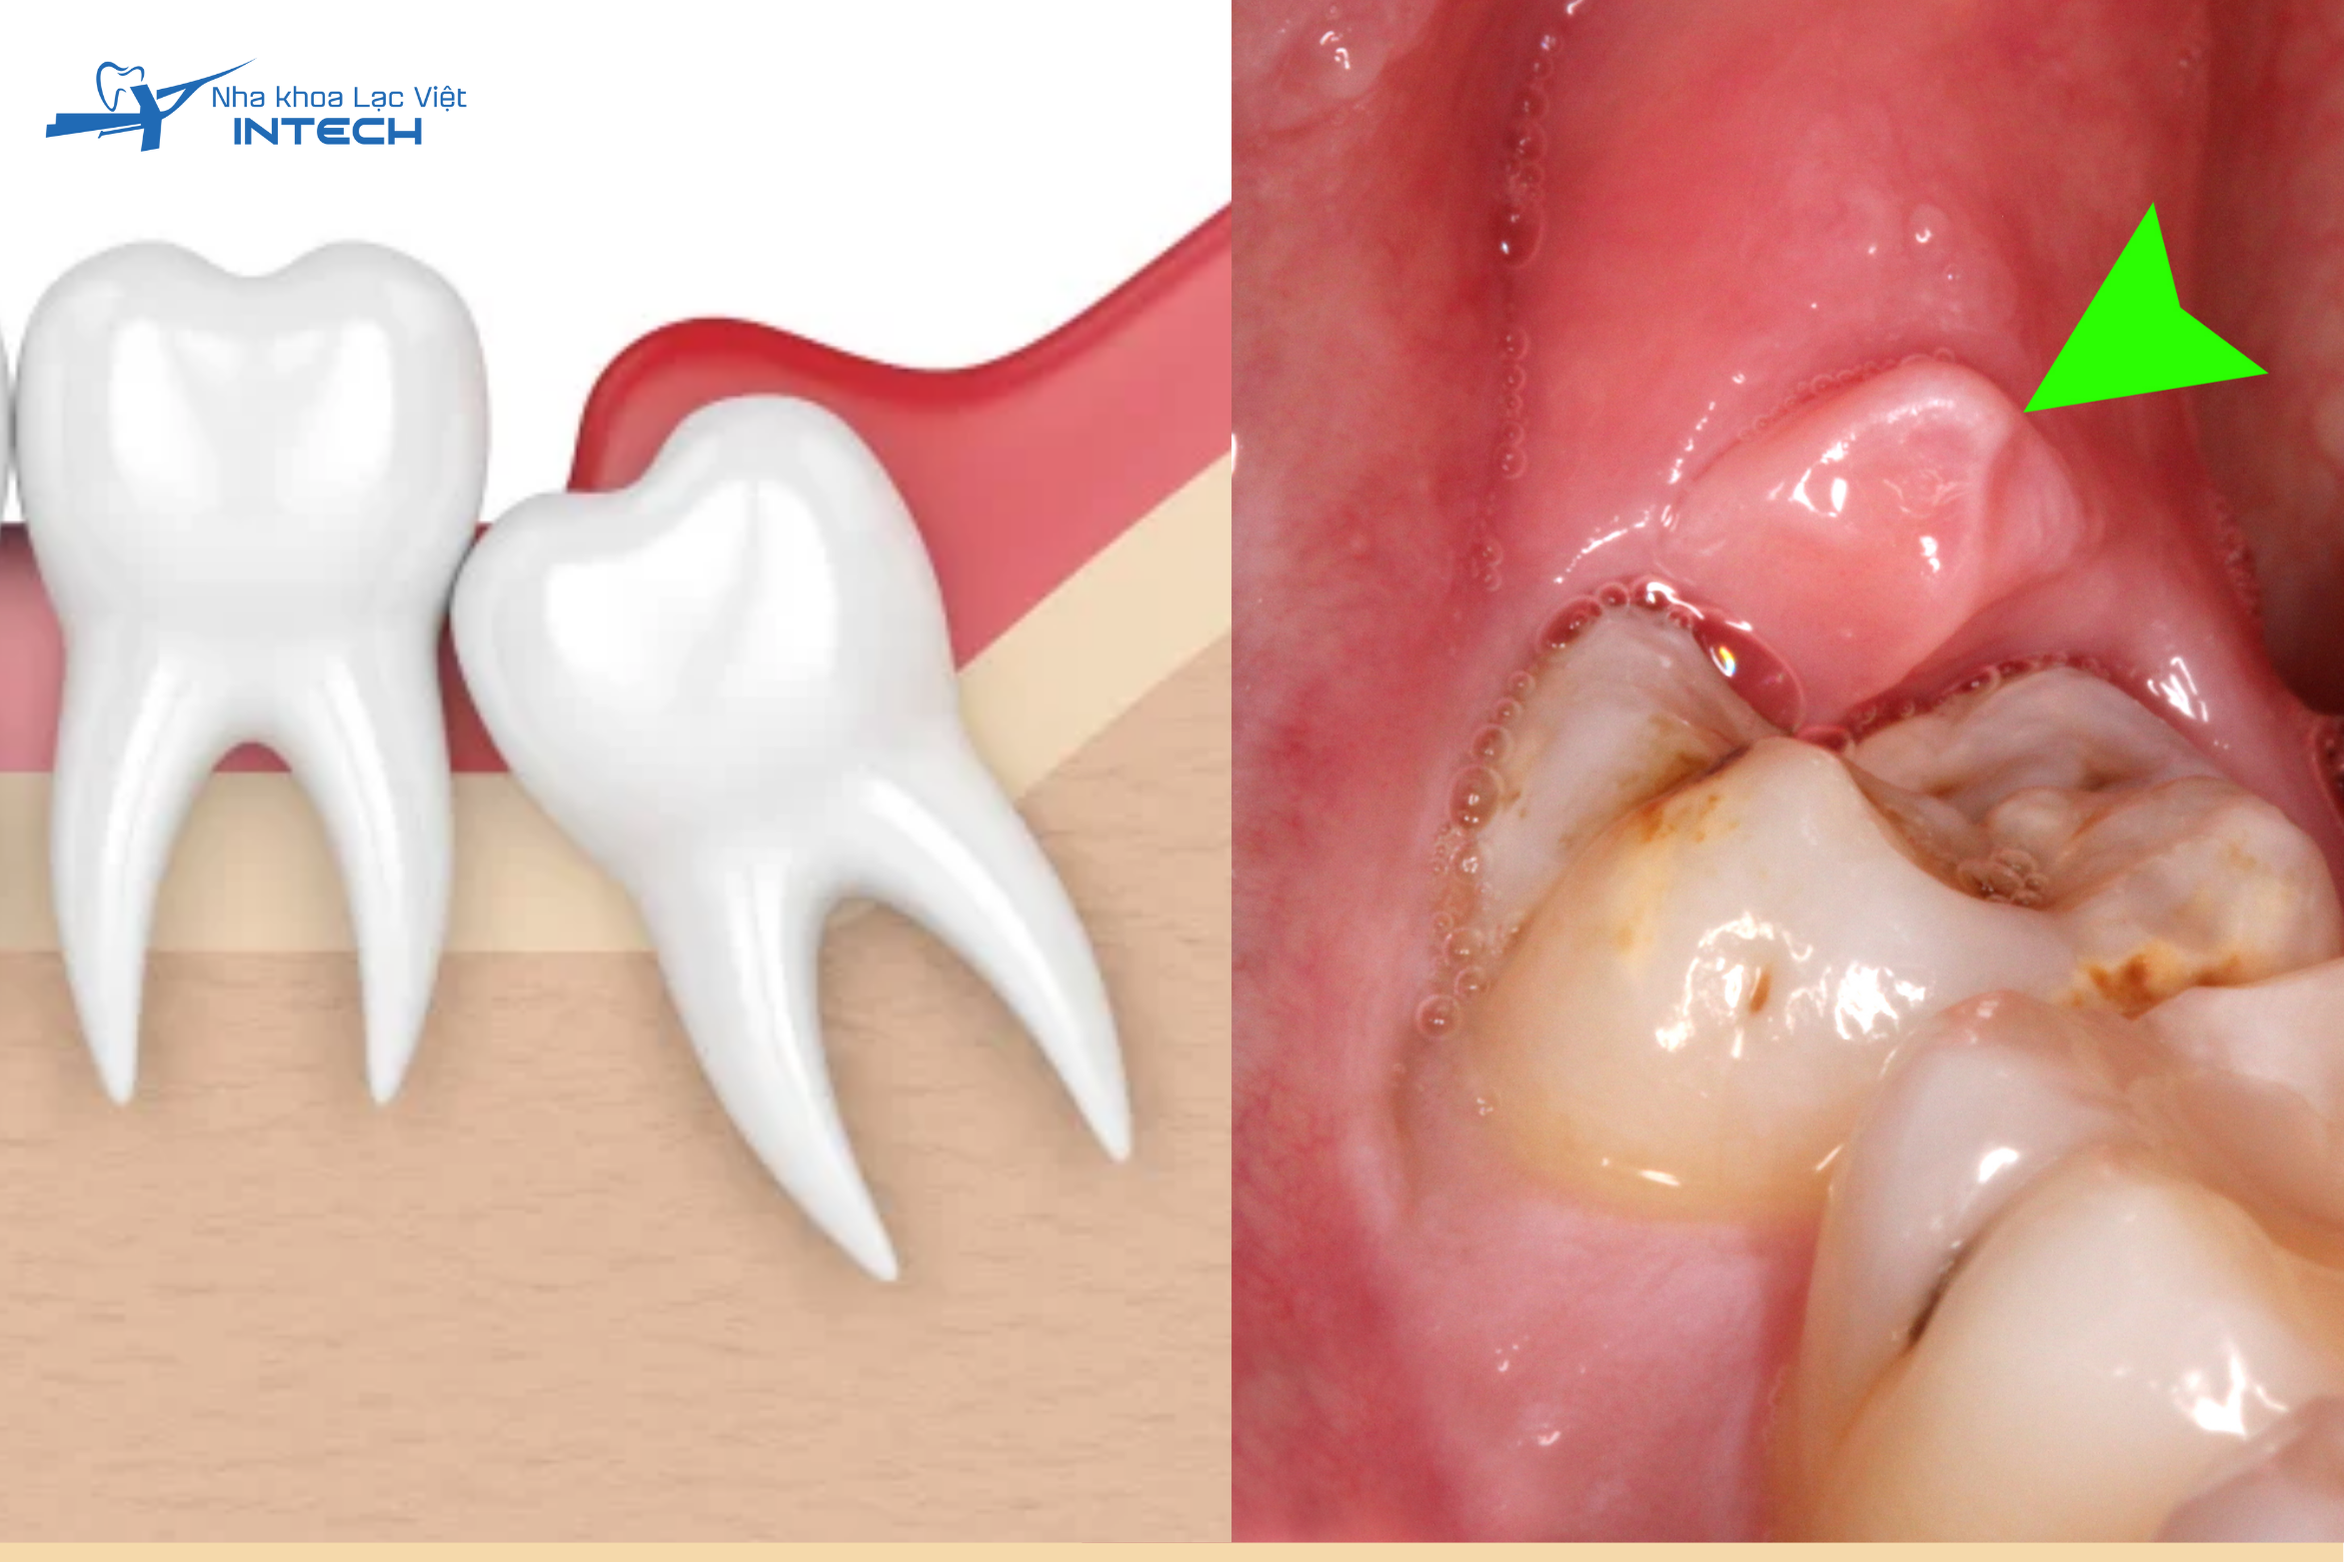

• Viêm lợi trùm: Khi răng khôn mọc không hết, một phần lợi sẽ che phủ và dễ viêm nhiễm, gây sưng tấy, đau đớn.

Khi răng khôn mọc không hết một phần lợi sẽ che phủ và dễ viêm nhiễm gây sưng tấy đau đớn